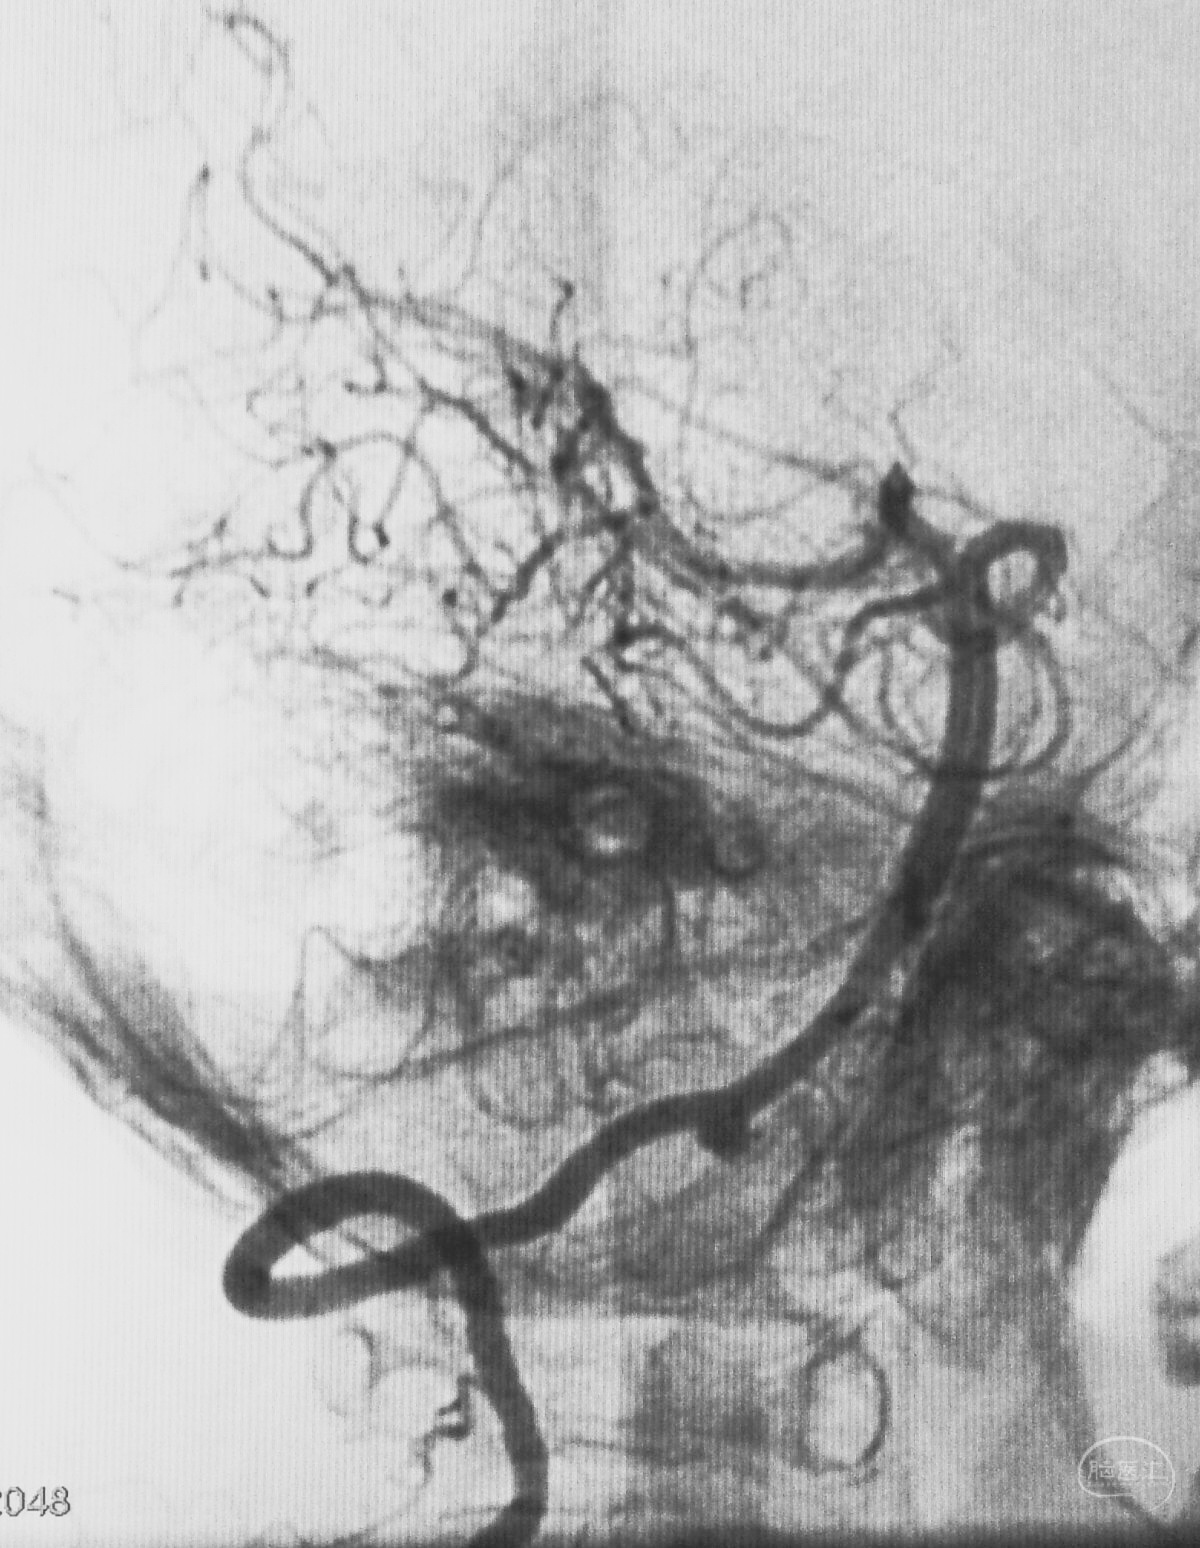

病例二,右侧椎动脉V4段夹层动脉瘤,以头痛入院,21个月前有SAH史。

右椎动脉造影三维重建

Echelon 10微导管头无论塑成C形还是S形,均无法稳定于动脉瘤腔内,遂使用回马枪技术,使微导管成襻通过,管头折返入瘤腔。